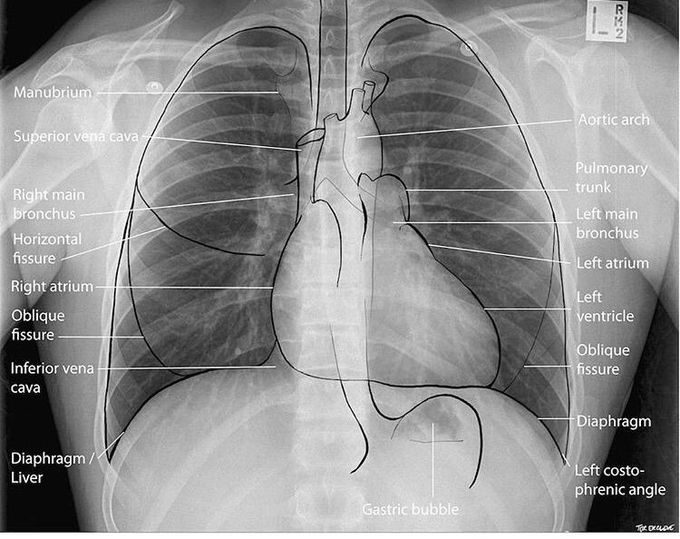

Normal Chest XRay • LITFL Medical Blog • Labelled Radiology What Can Be Found In A Chest X Ray The growth might be cancer, but it could also be any number of benign or. There are no visible nodules, tumors or masses. The interpretation of a chest film. In fact every radiologst should be an expert in chest film reading. What Can Be Found In A Chest X Ray.